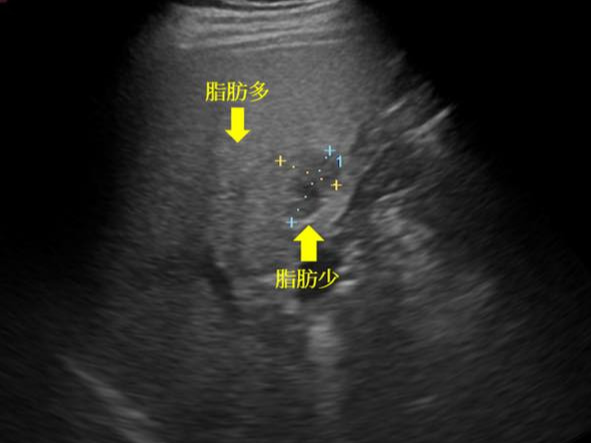

간은 복부 초음파의 핵심 관찰 대상입니다. 간 실질의 에코 패턴을 통해 지방간 여부를 비교적 정확하게 판단할 수 있으며, 지방 침착의 정도에 따라 경증, 중등도, 중증으로 나누어 추정이 가능합니다. 또한 간낭종, 간혈관종과 같은 양성 종양은 초음파에서 특징적인 모양으로 관찰되는 경우가 많아 추적 관찰 여부를 결정하는 데 도움이 됩니다. 간경변이 진행된 경우에는 간 표면이 불규칙해지고 비장이 커지는 소견이 함께 나타날 수 있으며, 이는 만성 간질환의 중요한 단서가 됩니다. 다만 간암의 경우 초기 병변은 초음파에서 놓칠 수 있어, 고위험군에서는 CT나 MRI와 병행하는 것이 일반적입니다.

복부 초음파의 가장 큰 장점은 안전성과 접근성입니다. 방사선 노출이 없고, 검사 시간이 짧으며, 반복 검사에 대한 부담이 적습니다. 또한 비교적 저렴한 비용으로 복부 장기의 전반적인 상태를 파악할 수 있어 1차 선별 검사로 매우 유용합니다. 반면 검사자의 숙련도에 따라 결과의 질이 달라질 수 있고, 비만이나 장내 가스가 많은 경우에는 관찰이 제한될 수 있다는 한계가 있습니다.